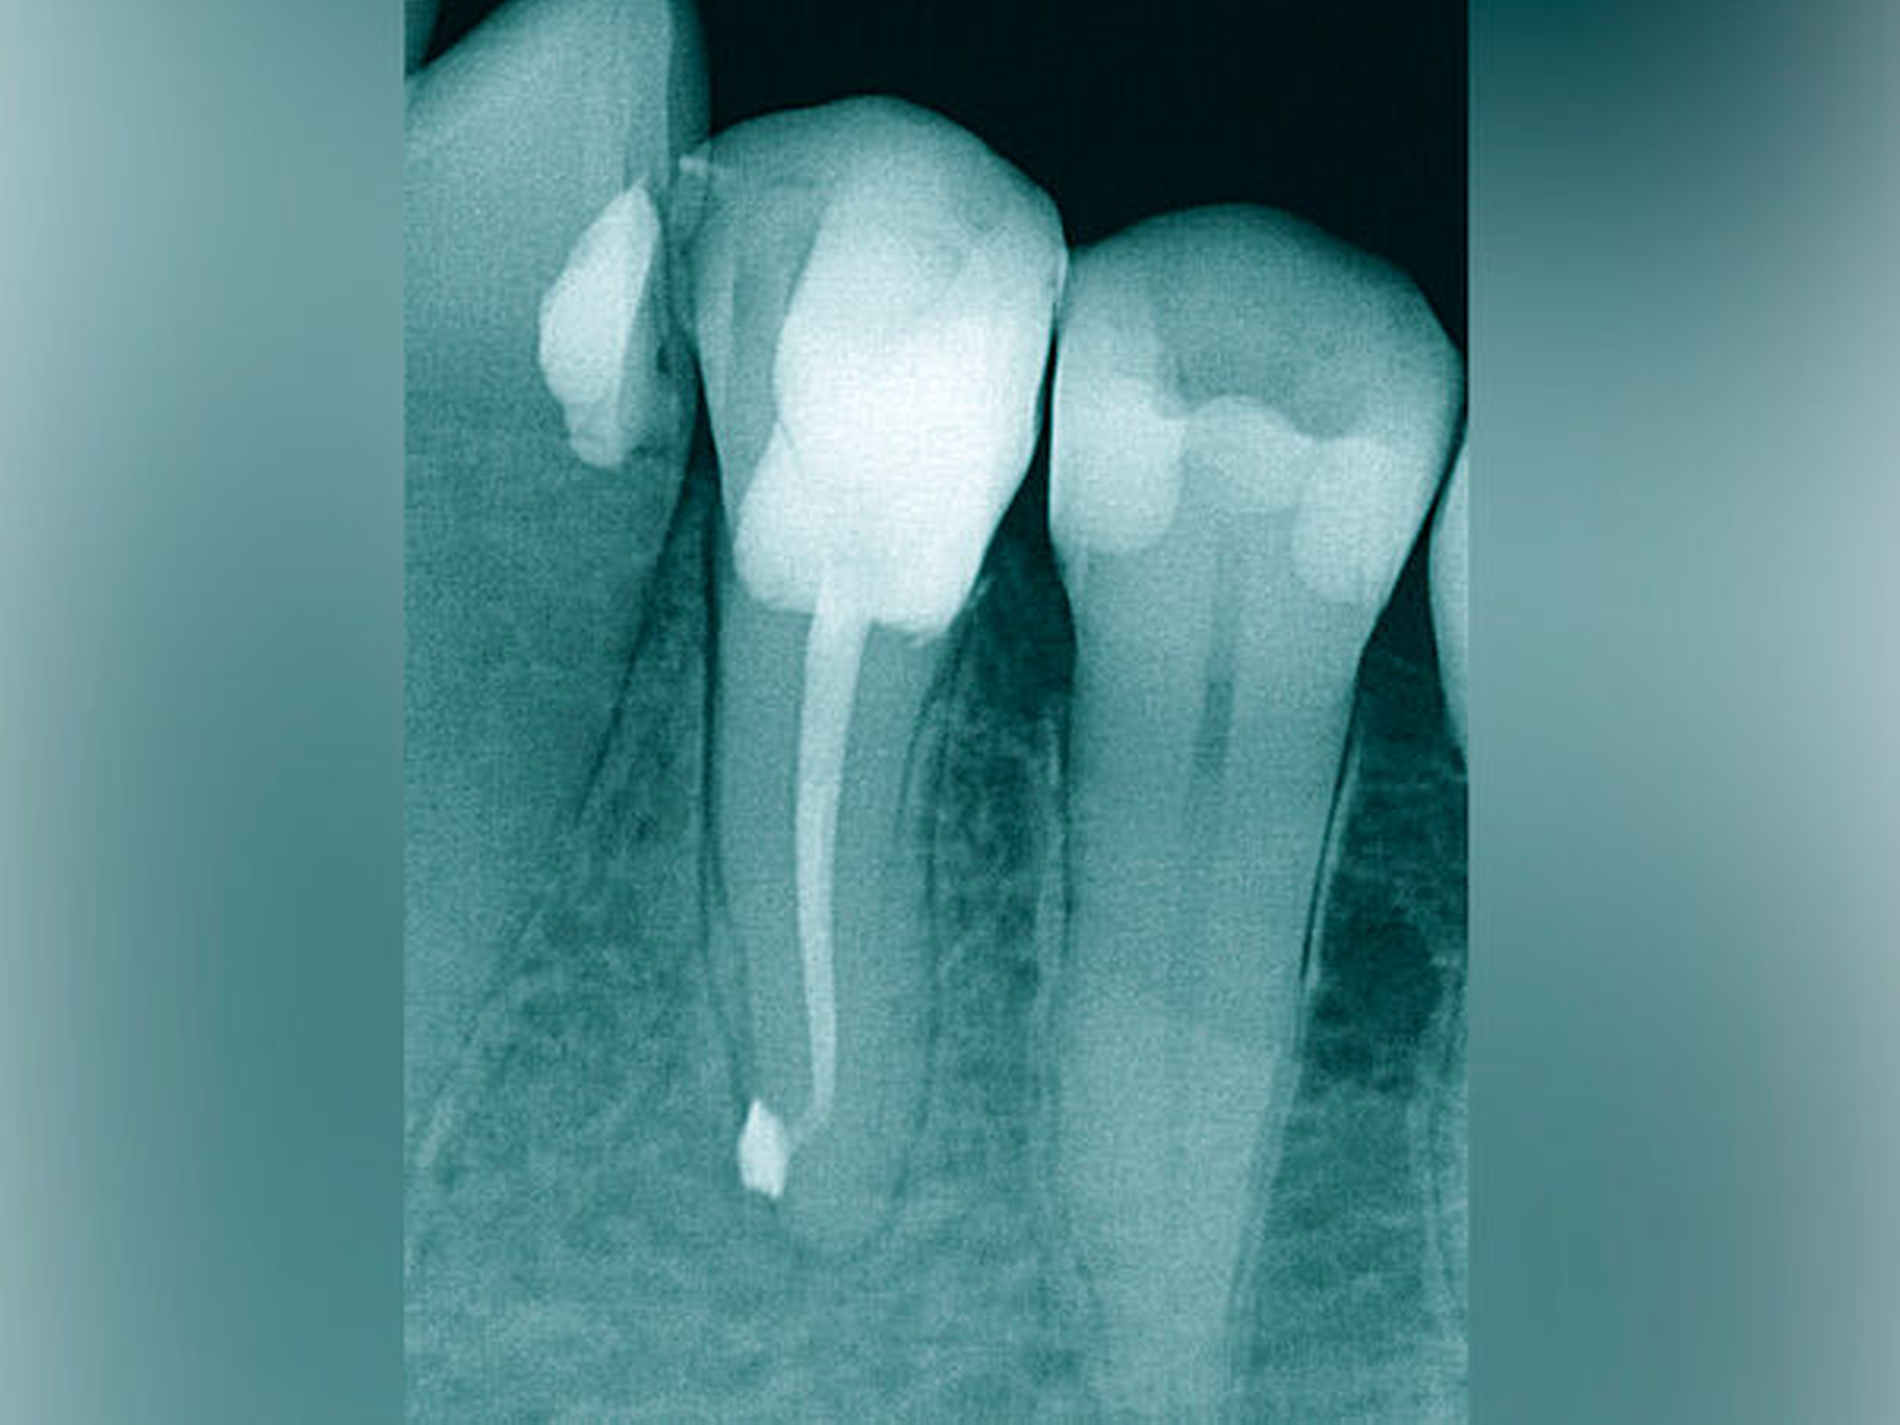

Die Schwierigkeit in der Therapie nimmt zu, wenn die Wurzelkanalkrümmung mehr als 30 Grad beträgt, der Krümmungsradius abnimmt (enge Krümmung) oder Mehrfachkrümmungen vorliegen [Duke et al., 2015; Pedulla et al., 2020]. Typisch für Mehrfachkrümmungen sind vor allem mesiale Wurzelkanäle unterer Molaren (Abbildung 4).

Sollte eine Konfluenz beider mesialer Wurzelkanäle am unteren Molaren vorliegen, kommt es zu einem abrupten Richtungswechsel und Instrumente können leichter frakturieren oder Stufen präparieren, so dass die Arbeitslänge nicht mehr erreicht werden kann.